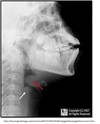

What is the radiographic sign of Epiglottitis?

Thickened epiglottis (Thumb sign) on a lateral soft tissue neck

What pathology is seen here?

Eppiglottitis (see the red arrow pointing to thumb print sign)